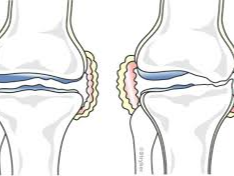

나이가 들면 관절 사이 연골이 점차 닳아 없어지면서 뼈와 뼈가 직접 맞닿아 통증을 유발합니다. 특히 무릎은 체중을 지탱하는 관절로써 손상되기 쉬우며, 다음과 같은 증상이 있다면 인공관절 수술이 필요할 수 있습니다.

이런 경우에는 무릎 인공관절 치환술이 가장 효과적인 치료법으로 여겨지며, 수술 후에는 통증 완화 및 활동 능력 회복이 가능합니다.